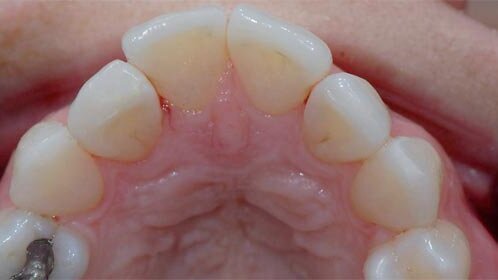

A 36-year-old female patient presented for a consultation concerning her anterior aesthetics. She was not pleased with the palatal position of her right lateral incisor (Fig. 1). Owing to her profession—she works as a violinist with regular TV appearances—she often performs in studios, where the lights accentuate the dark space in the area of the lateral incisor. She also wanted to correct the pointed incisal edges of her upper canines (Fig. 2). Apart from reporting these specific problems, the patient requested an overall enhancement of her smile. A main concern of the patient was that all treatment should be done without preparing any of her teeth.

Figs. 1 & 2: Pre-op view of the smile (Fig. 1). Pre-op view. Note the incisal edges (Fig. 2).

Figs. 3–8: Frontal view of the cast (Fig. 3). Occlusal view of the cast (Fig. 4). Frontal view of the diagnostic wax-up (Fig. 5). Occlusal view of the wax-up (Fig. 6). Frontal view of the veneers in the cast (Fig. 7). Occlusal view of the veneers on the cast (Fig. 8).

A diagnostic wax-up was made (Figs. 5 & 6) for evaluative purposes. We decided to elongate teeth 11 and 21 by adding and simultaneously shaping up the incisal edges, and increasing the bulk of the contour facially, to complement the appearance. We also added bulk to tooth 12, to make it part of the arch, and shaped the facial contour of tooth 22 similarly. In addition, we added a little bit of bulk mesially to the incisal edges of the canines, in order to minimise the pointed incisal edges. All changes in the contour were additive and no teeth needed to be prepared. The veneers were manufactured in the laboratory using IPS d.SIGN porcelain (Ivoclar Vivadent), keeping the same shape as the wax-up model. A full facial coverage porcelain veneer was manufactured in teeth 12 and 22. Very thin porcelain edges were fabricated in teeth 13, 11, 21, and 23 (Figs. 7 & 8).